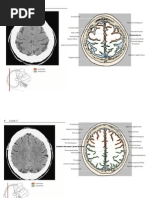

Diagnosis

- computed tomography (CT) head findings of small punctate

hemorrhages to white matter tracts can indicate diffuse axonal injury in

the setting of an appropriate clinical presentation.

- Currently, magnetic resonance imaging (MRI), specifically diffuse

tensor imaging (DTI), is the imaging modality of choice for diagnosis of

diffuse axonal injury

Bradley’s Neurology in Clinical Practice.